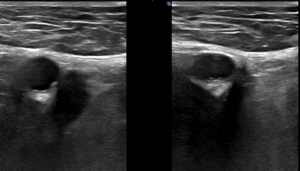

Ecografía Modo B (SIN Y CON compresión externa) de los miembros inferiores en el triángulo femoral.